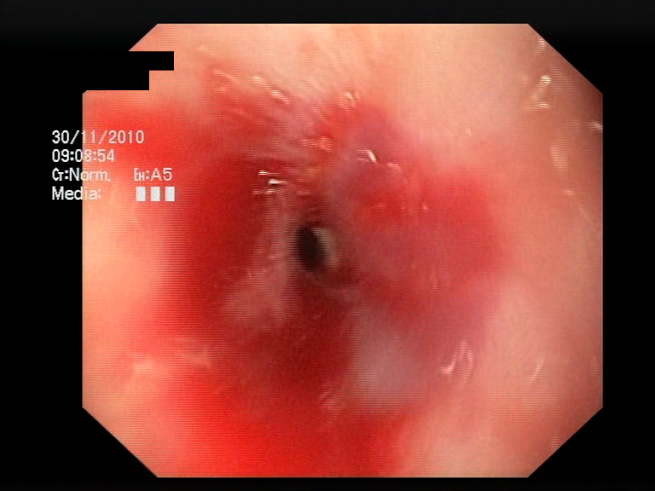

5.3. Bleeding Area Localization

The baseline models and the proposed feature-extended models were also evaluated in terms of providing potential explanations for classification predictions. In this case, the expected form of an explanation is the location of the bleeding areas detected by the classifier. To evaluate the quality of the localizations, a subset of the test set was used, consisting of all images for which blood area masks were available in the dataset. The subset consists of 25 test images with segmentation masks. A sample image with the associated blood area mask is presented in Figure 5. For each of the 25 test images, localizations were generated for all the evaluated models using a set of approaches and compared against the reference segmentation masks.

Figure 5.

Sample test set image and the associated blood area mask.